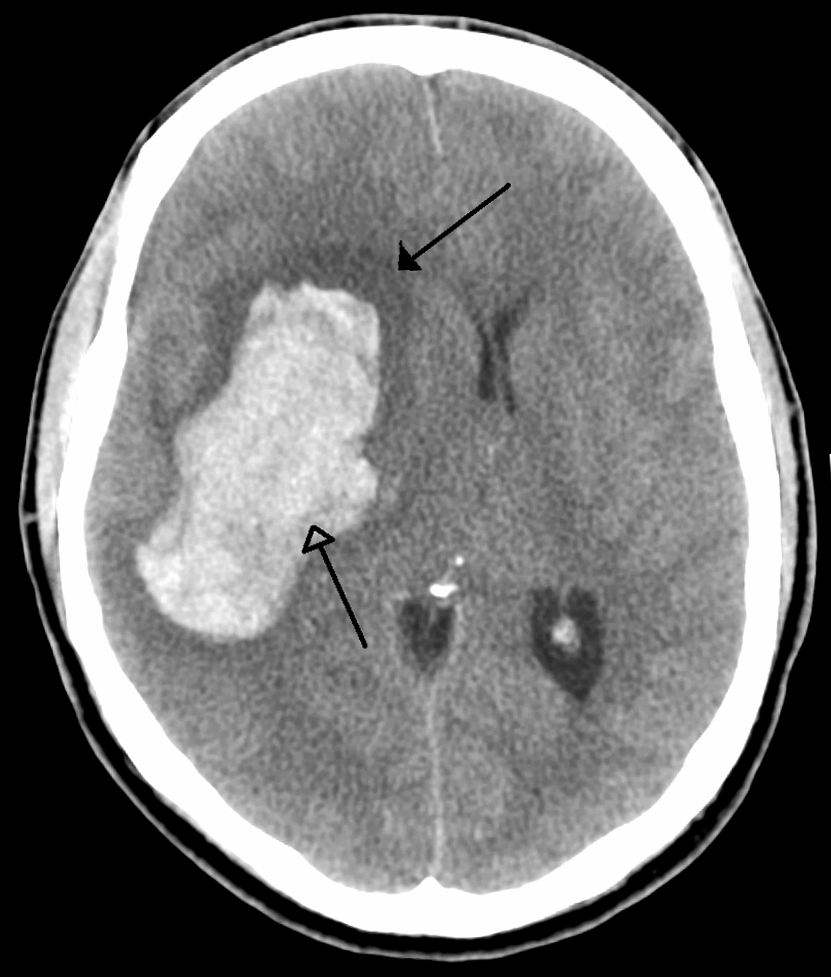

One devastatingly common disease that neurosurgeons treat is intracerebral hemorrhage, or ICH, which is when bleeding occurs inside the skull. In Chicago, where I am training, there are five major academic medical centers that provide specialty care for diseases like ICH: the medical centers of Loyola University, Rush University, Northwestern University, the University of Chicago, and the University of Illinois. And, according to a study published earlier this month, led by Dr. Andrew Naidech, there are measurable differences in how ICH is treated at these different institutions.

IN THE PHOTO: A CT scan of the brain showing intracranial hemorrhage (ICH). The arrows point to the bleeding inside the brain. Would small-area variation cause doctors out of the 5 academic medical centers in Chicago to all perform ICH surgery differently? Photo credit: WikiMedia Commons

Any injury to the brain can cause seizures, and ICH is no exception. For a long time, it was standard for patients with brain bleeding to take anti-seizure medications, but it wasn’t clear which anti-seizure drug worked best for ICH. Then, in 2009, a study showed that people taking one common seizure medication do not recover from their injuries as well as people taking another. In response to this study, many doctors stopped prescribing the medication that was linked to poor recovery, and started prescribing the medication that was linked to good recovery. However, Dr. Naidech’s study showed that patients at each major medical center in Chicago were treated very differently. Patients at one hospital were almost five times more likely to get the drug linked to good recovery than patients at another. Each medical center is staffed with experts distinguished in their fields, yet patients at one of them receive markedly different treatment than patients at another.